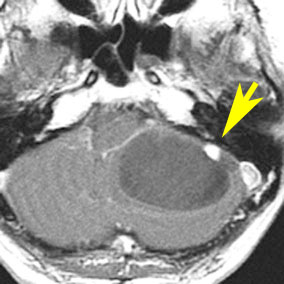

左右の写真は異なった患者さんのものです。両者ともに,大きな嚢胞(水たまり)を伴う小脳内部の小さな血管芽腫です。右の方に小さく白い塊(黄色の矢印)が見えるのですが,それだけが腫瘍で,濃い灰色に見える部分はのう胞といって液体がたまっているだけです。

これはとても(といっては何ですが比較的に)簡単な手術例です。小脳失調によるふらつきや水頭症よる頭痛と嘔吐などを出しますが,手術後に症状は改善します。

一般に小脳半球という場所にできたものは大きくても手術の成功率はとても高いです。小さいものでは場所と症状によってはガンマナイフなどの放射線治療も有効なことがあります。しかし,手術で摘出できるものは摘出した方が確実に治ります。

フォン・ヒッペル・リンドウ病の患者さんの脊髄(胸髄)にできた血管芽腫です。上下の脊髄が腫れたり,脊髄の中に空洞(腫瘍のう胞あるいは脊髄空洞症といいます)ができます。 手術治療は症状が出るまで,あるいは症状がかなり強くなってからしかしません。なぜなら,たくさんできる(多発)することが多くて,複数回の手術になってしまうこともあるからです。手術をするたびに,四肢のしびれや麻痺などの後遺症がのこる可能性もあるので,この手術は,脊髄腫瘍の手術経験が相当にたくさんある脳外科医にしかできません。